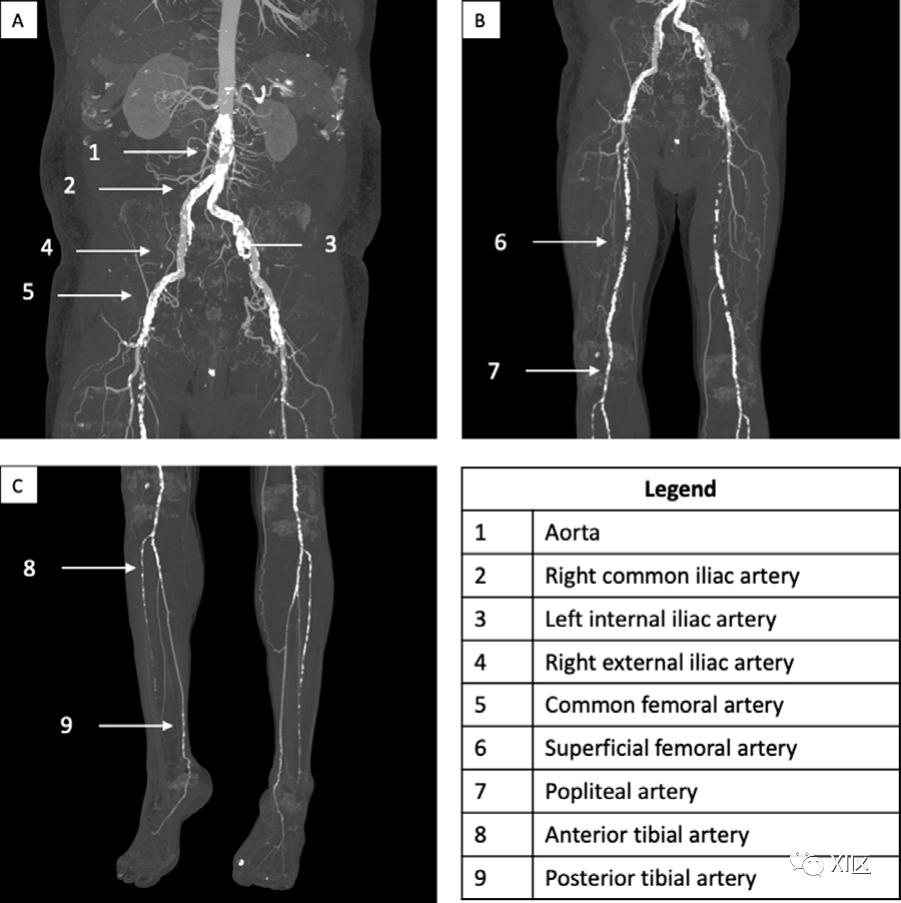

下肢血管在解剖学上可分为流入(髂动脉)、流出(股动脉)和径流(胫腓)动脉。流入血管包括肾下腹主动脉,在第四腰椎体处分叉为左、右髂总动脉。虽然这些血管解剖学变化相对较少,但腹主动脉的高分叉(在第三腰椎体)是一种血管变异,在临床上对腹部和脊柱手术很重要。图1和图2展示了下肢的经典动脉解剖结构。每条髂总动脉被分为髂外动脉和髂内动脉。髂内动脉的分支有很大的变化。需要注意的一个突出的解剖学变化是,闭孔动脉,通常是髂内动脉前分支的一个分支,沿骨盆前下方通过,可以通过附属闭孔动脉或死亡冠(corona mortis)与髂外动脉吻合连接。由于盆腔损伤后有可能出现危及生命的出血,因此死亡冠的存在具有临床意义,也可用于手术计划。

图5 61岁男性,患有外周动脉疾病。A)冠状位上的最大密度投影CTA图像显示主动脉钙化(1)、髂总动脉(2)、髂内动脉(3)、髂外动脉(4)和股总动脉(5)的双侧钙化。B)冠状位最大密度投影CTA图像显示股浅动脉(6)和腘动脉(7)钙化。C)冠状位最大密度投影CTA图像显示胫骨前动脉(8)和胫骨后动脉(9)钙化。